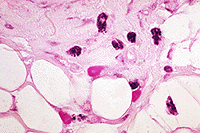

1. Adipocito (o célula adiposa) es una célula especializada en el almacenamiento de grasas neutras.

2. Tejido conectivo adiposo

1. Similar al tejido Conjuntivo laxo pero con menos fibras. Sus células características, denominadas adipocitos, se especializan en los almacenamientos de lípidos. Se localiza bajo la dermis, rodeando a órganos internos como el riñón y en el interior de la parte central de los huesos largos (médula ósea amarilla o tuétano). Su función es de reserva energética y como aislante térmico y mecánico